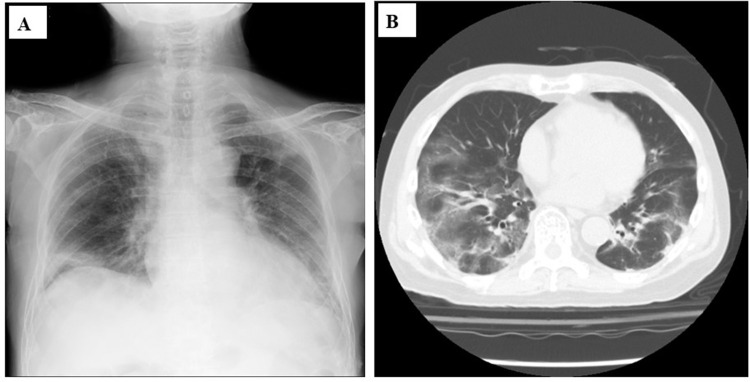

Three cases of severe influenza that required ventilator management in the 2024-2025 season, which was a major influenza season in Japan, are presented. Case 1: A 54-year-old man with obesity developed lobar pneumonia as a result of severe community-acquired pneumonia (CAP) secondary to methicillin-susceptible Staphylococcus aureus (MSSA), as confirmed on sputum culture. The nasal swab was positive for influenza A antigen. Intravenous peramivir and piperacillin/tazobactam were administered for 2 days followed by lascufloxacin and linezolid for 2 weeks. Veno-venous extracorporeal membrane oxygenation (VV-ECMO) was also performed. Case 2: A 63-year-old man with multiple myeloma and chronic kidney disease developed severe pneumonia as a result of CAP. Although influenza A antigen was detected, no bacteria were isolated from his specimens. He showed severe hypoxia and massive ground-glass opacities (GGOs) in both lung fields, but he recovered after administration of peramivir and levofloxacin with prednisolone for 2 days and 2 weeks, respectively, with non-invasive positive pressure support. Case 3: A 43-year-old man without any related medical history developed severe heart failure with mild bronchopneumonia and was admitted to our hospital. Acute heart failure caused by myocarditis and CAP due to influenza A were suspected and treated effectively with peramivir and a percutaneous ventricular assist device (IMPELLA), which involved an auxiliary circulating pump with veno-arterial ECMO (VA-ECMO) for 1 day and 2 weeks, respectively. In three middle-aged patients, influenza virus may have accelerated pneumonia/heart failure. All three patients had not received influenza vaccines and were not elderly. Although the emphasis on most vaccines has decreased after the COVID-19 pandemic appears to have subsided, we should stress the importance of influenza vaccines and improvement of critical care protocols, because severe influenza can be a concern for young and middle-aged adults during the influenza season after the post COVID-19 pandemic period.